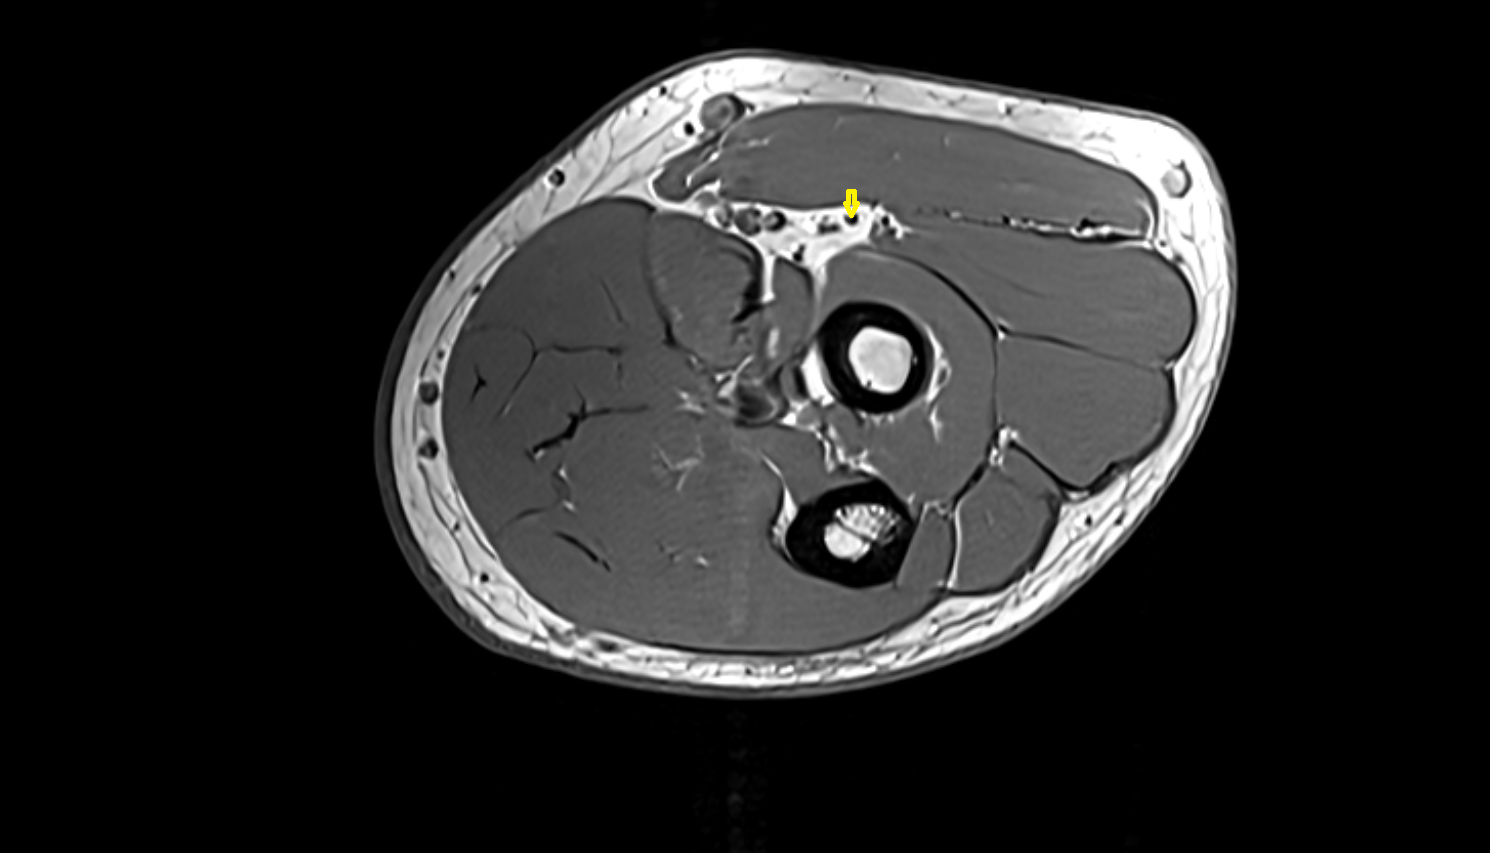

- Ankle joint